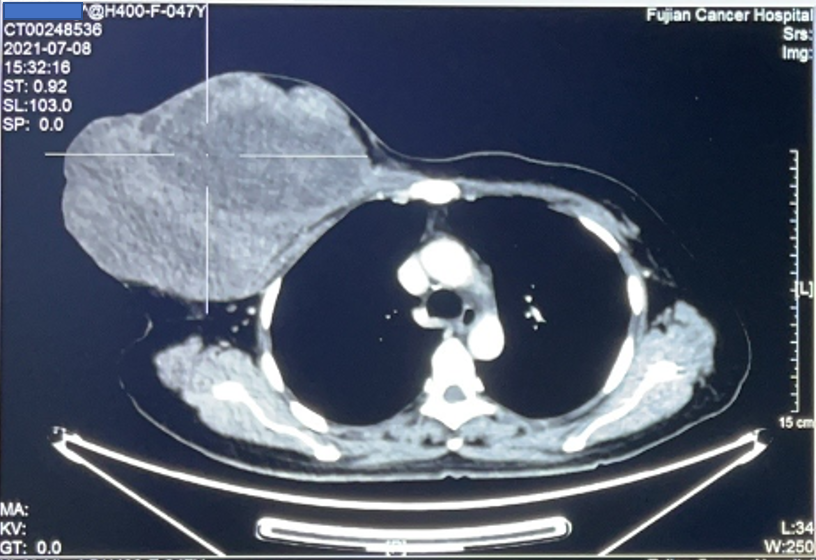

患者为47岁女性,发现右乳腺肿块半年,半年前肿块约网球大小,后逐渐生长增大到约25*22cm大小,伴有肿块的破溃、渗血、恶臭。患者深受困扰,痛苦不堪,辗转省内多家医院就诊,均被告知手术难度大、风险高。最后求诊我院,接诊患者后,乳腺肿瘤外科叶文飞主任组织团队成员游原瑜、黄志坚、黄秋艳、陈建医师、麻醉医师及护理团队,进行病情讨论和手术方案的制定。

胸壁恶性肿瘤常累及皮肤,胸大肌,深达肋骨表面,为减少复发需行肿瘤扩大切除,常造成胸壁巨大缺损。此类患者术后多需放化疗,为争取时间,采取快速可靠方法修复创面缺损具有重要意义。叶文飞主任考虑该患者创面巨大,不能直接缝合,需要进行肌皮瓣转移修复胸壁缺损。传统的背阔肌皮瓣因背部皮肤弹性较差,宽度一般不超过8 cm,否则供区不能直接拉拢缝合,甚至需植皮修复。因此巧妙设计,采用一蒂双瓣方式,设计背阔肌Kiss 皮瓣,两瓣对缝修复巨大创面,缩小了供区缺损,避免了植皮导致的一系列并发症。